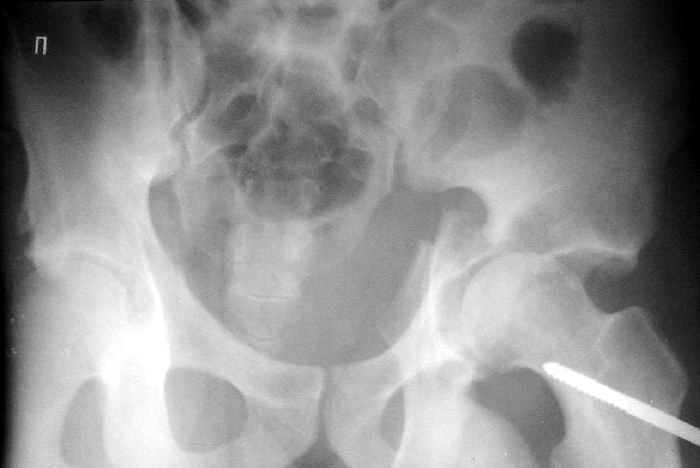

Пациент переведен в нашу клинику на 5 день после множественной травмы 25.01.2003 - двустороннее повреждение вертлужных впадин, разрыв левого крестцово-подвздошного сочленения. Вывихи обоих бедер. В месте первичного поступления подвздошный вывих правого бедра вправлен 26.01.2003, наложено вытяжение за левую вертельную область. Остеосинтез левой вертлужной впадины выполнен у нас 6.02.2003. Вопрос: надо ли синтезировать задне-верхний край правой вертлужной впадины?

правую впадину собрали здорово! Мои поздравления Рункову. Сами меня учили-учили, а где же запирательная проекция левой вертлужной

Поздравляю с отлично выполненой репозицией при остеосинтезе !

Согласен, что нужна вторая проекция.

Если нагрузка на конечности будет не ранее 5-6 недель,оперировать не стоит. Считаю, что эндопротезирование справа не будет нужным.